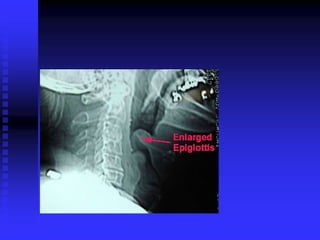

Epiglottitis

Epiglottitis: Pathophysiology

 Bacterial infection (Hemophilus influenza)

 Affects epiglottis, adjacent pharyngeal tissue

 Supraglottic edema

Complete Airway

Obstruction

Epiglottitis: Signs/Symptoms

 Rapid onset, severe distress in hours

 High fever

 Intense sore throat, difficulty swallowing

 Drooling

 Stridor

 Sits up, leans forward, extends neck slightly

 One-third present unconscious, in shock